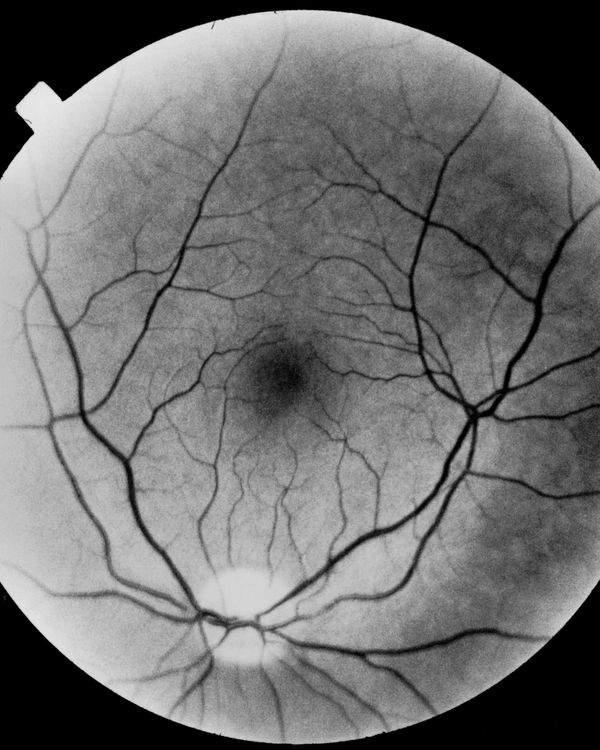

A visual narration of blindness is closely linked to memory, although the sight ceases, what remains is the entirety of the experiences that time offers us to the extent that we exist.

After all, after careful reflection, sight is not only the product of the activity of our eyes, it is also and above all the gaze of our mind through memory.

This visual nature of the past that gives shape to our memories, does not fit, in appearance, with blindness, yet, I wanted to probe this aspect, trying to tell the fear of losing sight.